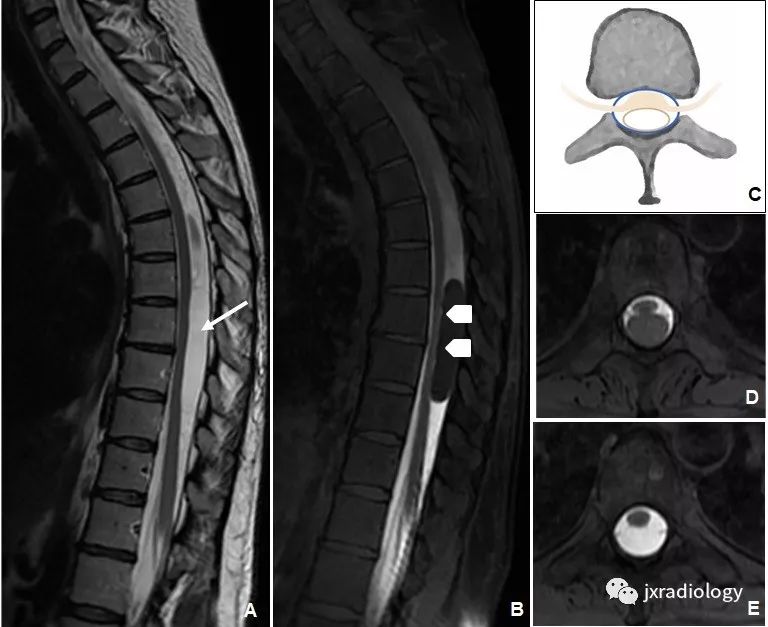

分类进展an update on the diagnosis and classification of cystic